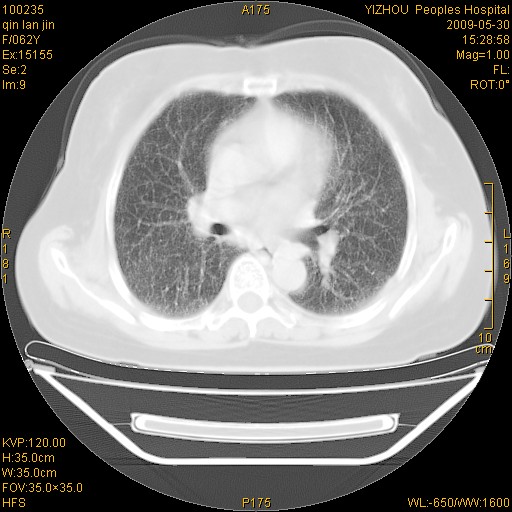

标题: CT20268:肺泡癌?间质性肺炎? [打印本页]

标题: CT20268:肺泡癌?间质性肺炎?

女,62岁,近二年经常咳嗽,近二个月,消瘦、乏力。

前面一张胸片是今天照的,后面一张胸片是去年9月份的。

弥漫性双肺间质纤维化。

两肺弥漫性间质性病变(间质性肺炎伴肺间质纤维化?)。

间质性肺炎伴肺间质纤维化。

纵隔淋巴结大,须排外癌性淋巴管炎